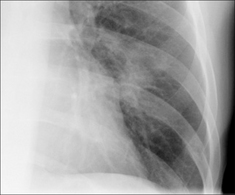

Figure 30.11 Mild haemoptysis due to bronchiectasis. The crowding of vessels and the prominent tramlines (thickened bronchial walls) at the right base raised the suggestion of bronchiectasis. Bronchiectasis was subsequently confirmed on CT.